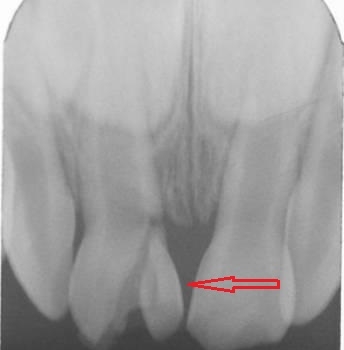

Daimi dişlərin travmatik zədələnmələri uşaq və yeniyetməlik dövründə olan şəxslərdə çox tez-tez rast gəlinir. Tac qırılmaları və lüksasiya travmalar içərisində ən çox rast gəlinənlərdir. Ancaq müxtəlif kliniki hallarda digər zədələnmə formaları da aşkar edilə bilir.

Doğru diaqnostika, müalicə planlaması və sonrakı dönəmdə izləmə uğurlu müalicəyə aparan ən başlıca faktorlardır. Diş travmaları və yaralanmaları tək diş bölgəsini əhatə edən məhdud, eyni zamanda çoxsaylı diş bölgəsini və çənənin alveol darağını əhatə edəcək qədər yayılmış formada rast gəlinə bilir. Çoxsaylı diş zədələnmələrində çox zaman fərqli dişlərdə fərqli növ zədələnmə şəkili aşkar edilə bilir ki, bu da hər bir dişə individual yanaşma və müalicə metodu tələb edir.